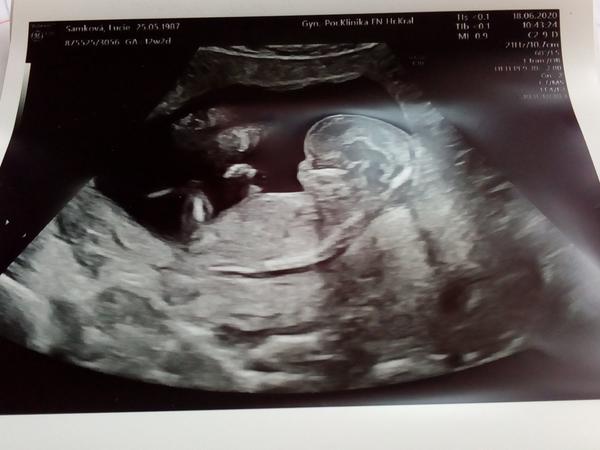

Ahoj maminky a budoucí maminky 😉 Prosím, poradila byste mi některá, co vidíte na fotce z ultrazvuku ve 20. týdnu za pohlaví? Určitě jste foteček viděly už mraky, proto vás žádám o radu...Nechci nikoho ovlivnit, proto svůj tip řeknu později 🙂 Děkuju moc!!!

@bexx Gratuluji, to to víte brzo, já furt nic ☹ moje doktorka má špatný UZ ale jdu ve CT na kontrolu tak se zkusím zeptat. No a jinak až za měsíc ve 20tt na velkém UZ to jdu jinam.